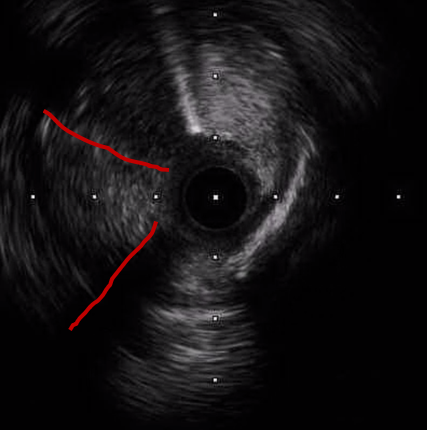

Inrefractory VT/VF arrest and cardiogenic shock, emergent culprit RCA PCI wasperformed under VA-ECMO and IABP. A Conquest Pro 12 GW crossed the distal RCACTO after failed attempts with Fielder FC and Gaia 2nd. Sequential POBA wasdone, followed by three BMS from RCA-M to RCA-PL, achieving TIMI 3 flow. Abrief attempt to wire LAD-P CTO with a Fielder XT-R failed, suggesting achronic occlusion, and the procedure was stopped due to instability. Afterneurological recovery, staged LAD CTO PCI was performed. Angiography confirmedLAD-P CTO with a blunt stump, severe LCX disease, and patent RCA stents.Antegrade wiring was initiated with an XB 3.5/7Fr GC. A Gaia 2nd entered aseptal branch using a Trek 1.2¡¿6 mm OTW BC. With APT 1.9Fr and Sasuke MCs,multiple GWs (XT-A, UB3, Conquest Pro 12) attempted proximal cap penetrationbut tracked into false lumens. IVUS from septal and D1 branches was used forcap clarification but remained inconclusive. Usingan IVUS-guided parallel-wire approach, a Progress 200T achieved true–false–truecrossing into distal LAD. Sequential 1.0–2.5 mm BC dilatation prepared thevessel. Given a Medina 1,1,1 LAD–D1 bifurcation, a DK-Crush technique waschosen. A Synergy 2.5¡¿48 mm DES was deployed from LAD-M to LAD-D, crushed,rewired, and optimized. A second 2.5¡¿48 mm DES was placed from LAD-P to D1,followed by kissing balloons and final POT. Final angiography showed TIMI 3flow with good expansion.